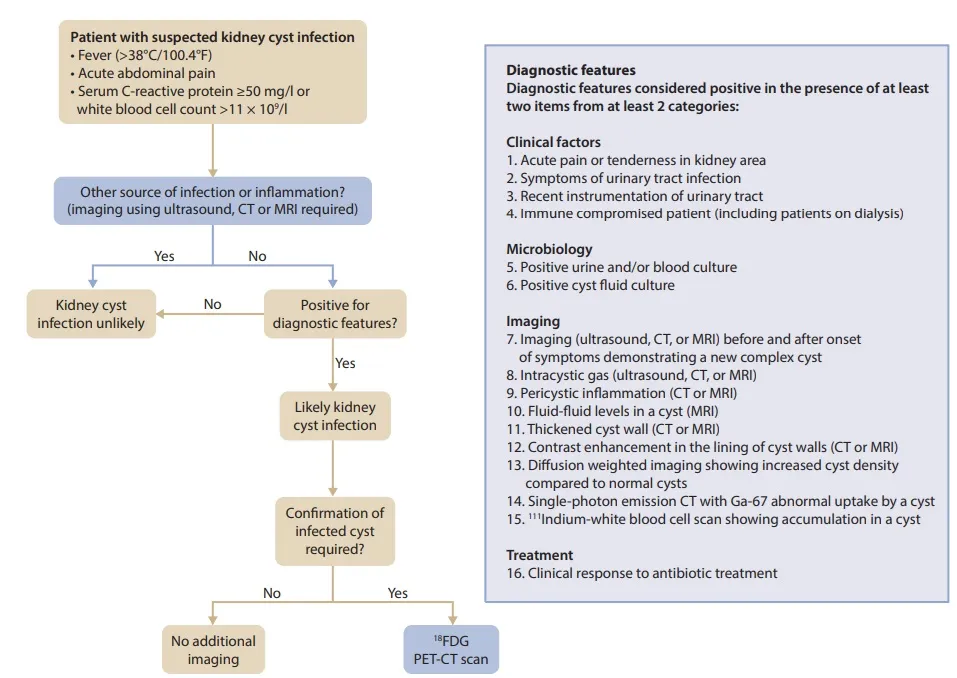

A investigação inclui história clínica, exame físico, EAS, urocultura com antibiograma, hemoculturas e, nos casos graves, exames de imagem. Confere essa figura muito prática

#### Confere esse o algoritmo abaixo super prático proposto pelo KDIGO para diagnóstico de infecção cística